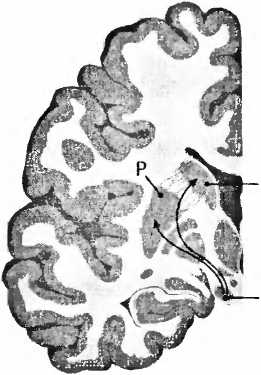

Для болезни Паркинсона характерно отмирание дофаминовых клеток в черной субстанции (substantia nigra) мозгового ствола (рис. 23). При вскрытии эта область мозга из-за пигментации клеток, вырабатывающих дофамин, выглядит как проходящая через мозговую ткань черная лента. И если эти клетки мертвы, их сразу же видно, как, например, при болезни Паркинсона. Тогда клетки не могут больше иннервировать полосатое тело (стриатум), моторную область в центре мозга, то есть снабжать ее нервными волокнами и управлять ею. Из-за недостатка в стриатуме дофамина возникают типичные для этой болезни расстройства движения. Что может быть логичнее, чем лечить эту болезнь заменой умерших клеток? В1987 году в ведущем профессиональном журнале The New England Journal of Medicine[89] появилась статья мексиканского врача Мадрасо, в которой он сообщал о поразительном улучшении у больного паркинсонизмом после аутотрансплантации ткани дофаминсодержащих клеток надпочечников в хвостатое ядро (nucleus caudatus, рис. 23). В ближайшие два года сообщение привело к лавине из 200 подобных трансплантаций. Но операция оказалась неэффективной, и в течение двух лет после нее 20 % пациентов умерли. Исследование мозга умерших показало, что трансплантированная из надпочечников ткань в мозге не прижилась. В стриатуме были видны только шрамы. Многообещающие результаты Мадрасо были основаны, вероятно, на непрофессионально проведенных исследованиях в сочетании с эффектом плацебо (см. XVII.4).

Рис. 23. При болезни Паркинсона пигментированные черным клетки, производящие дофамин в черной субстанции (SN), умирают и уже больше не могут управлять моторной областью — полосатым телом стриатумом (Р — putamen, скорлупа; NC — nucleus caudatus, хвостатое ядро).